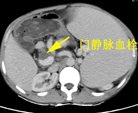

患者朱XX,男,49岁,因“上腹部胀痛2天”2015年入院,查体:脾脏肋下15cm。入院时血液学检查:白细胞明显降低仅为0.8X109/L,血小板明显降低仅为 23X109/L。入院时彩超:脾大Ⅲ度,门静脉、脾静脉内异常回声(考虑血栓形成),腹腔积液。

入院CT

临床诊断:肝硬化、门静脉高压 门静脉、脾静脉血栓 脾功能亢进 食管、胃底静脉曲张(重度)门脉高压性胃病